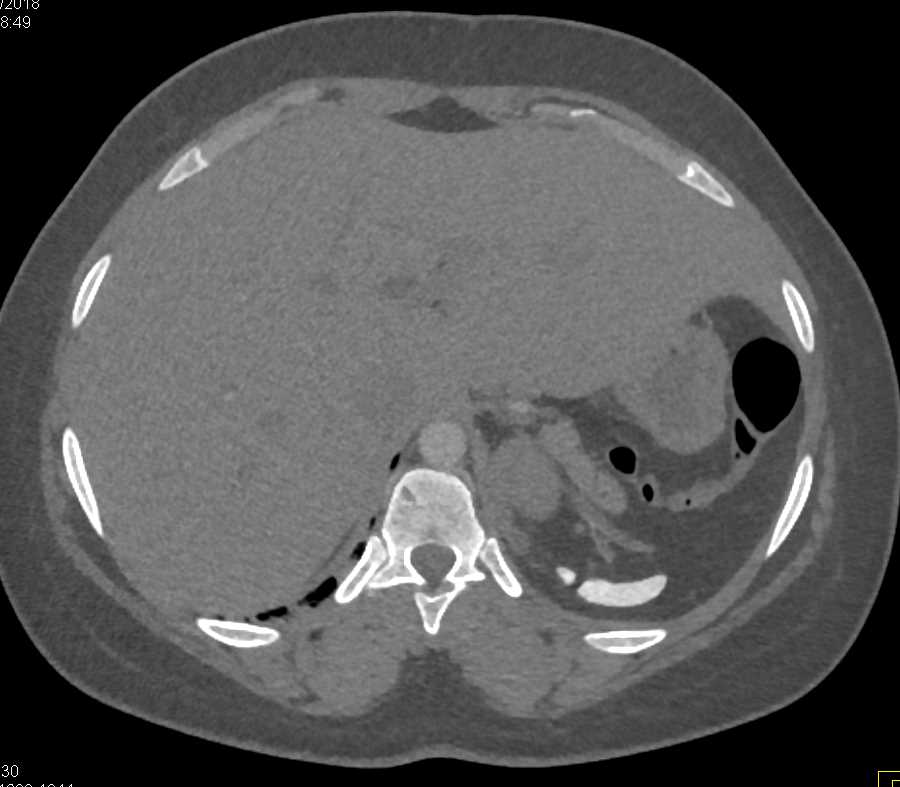

Gaucher's Spleen